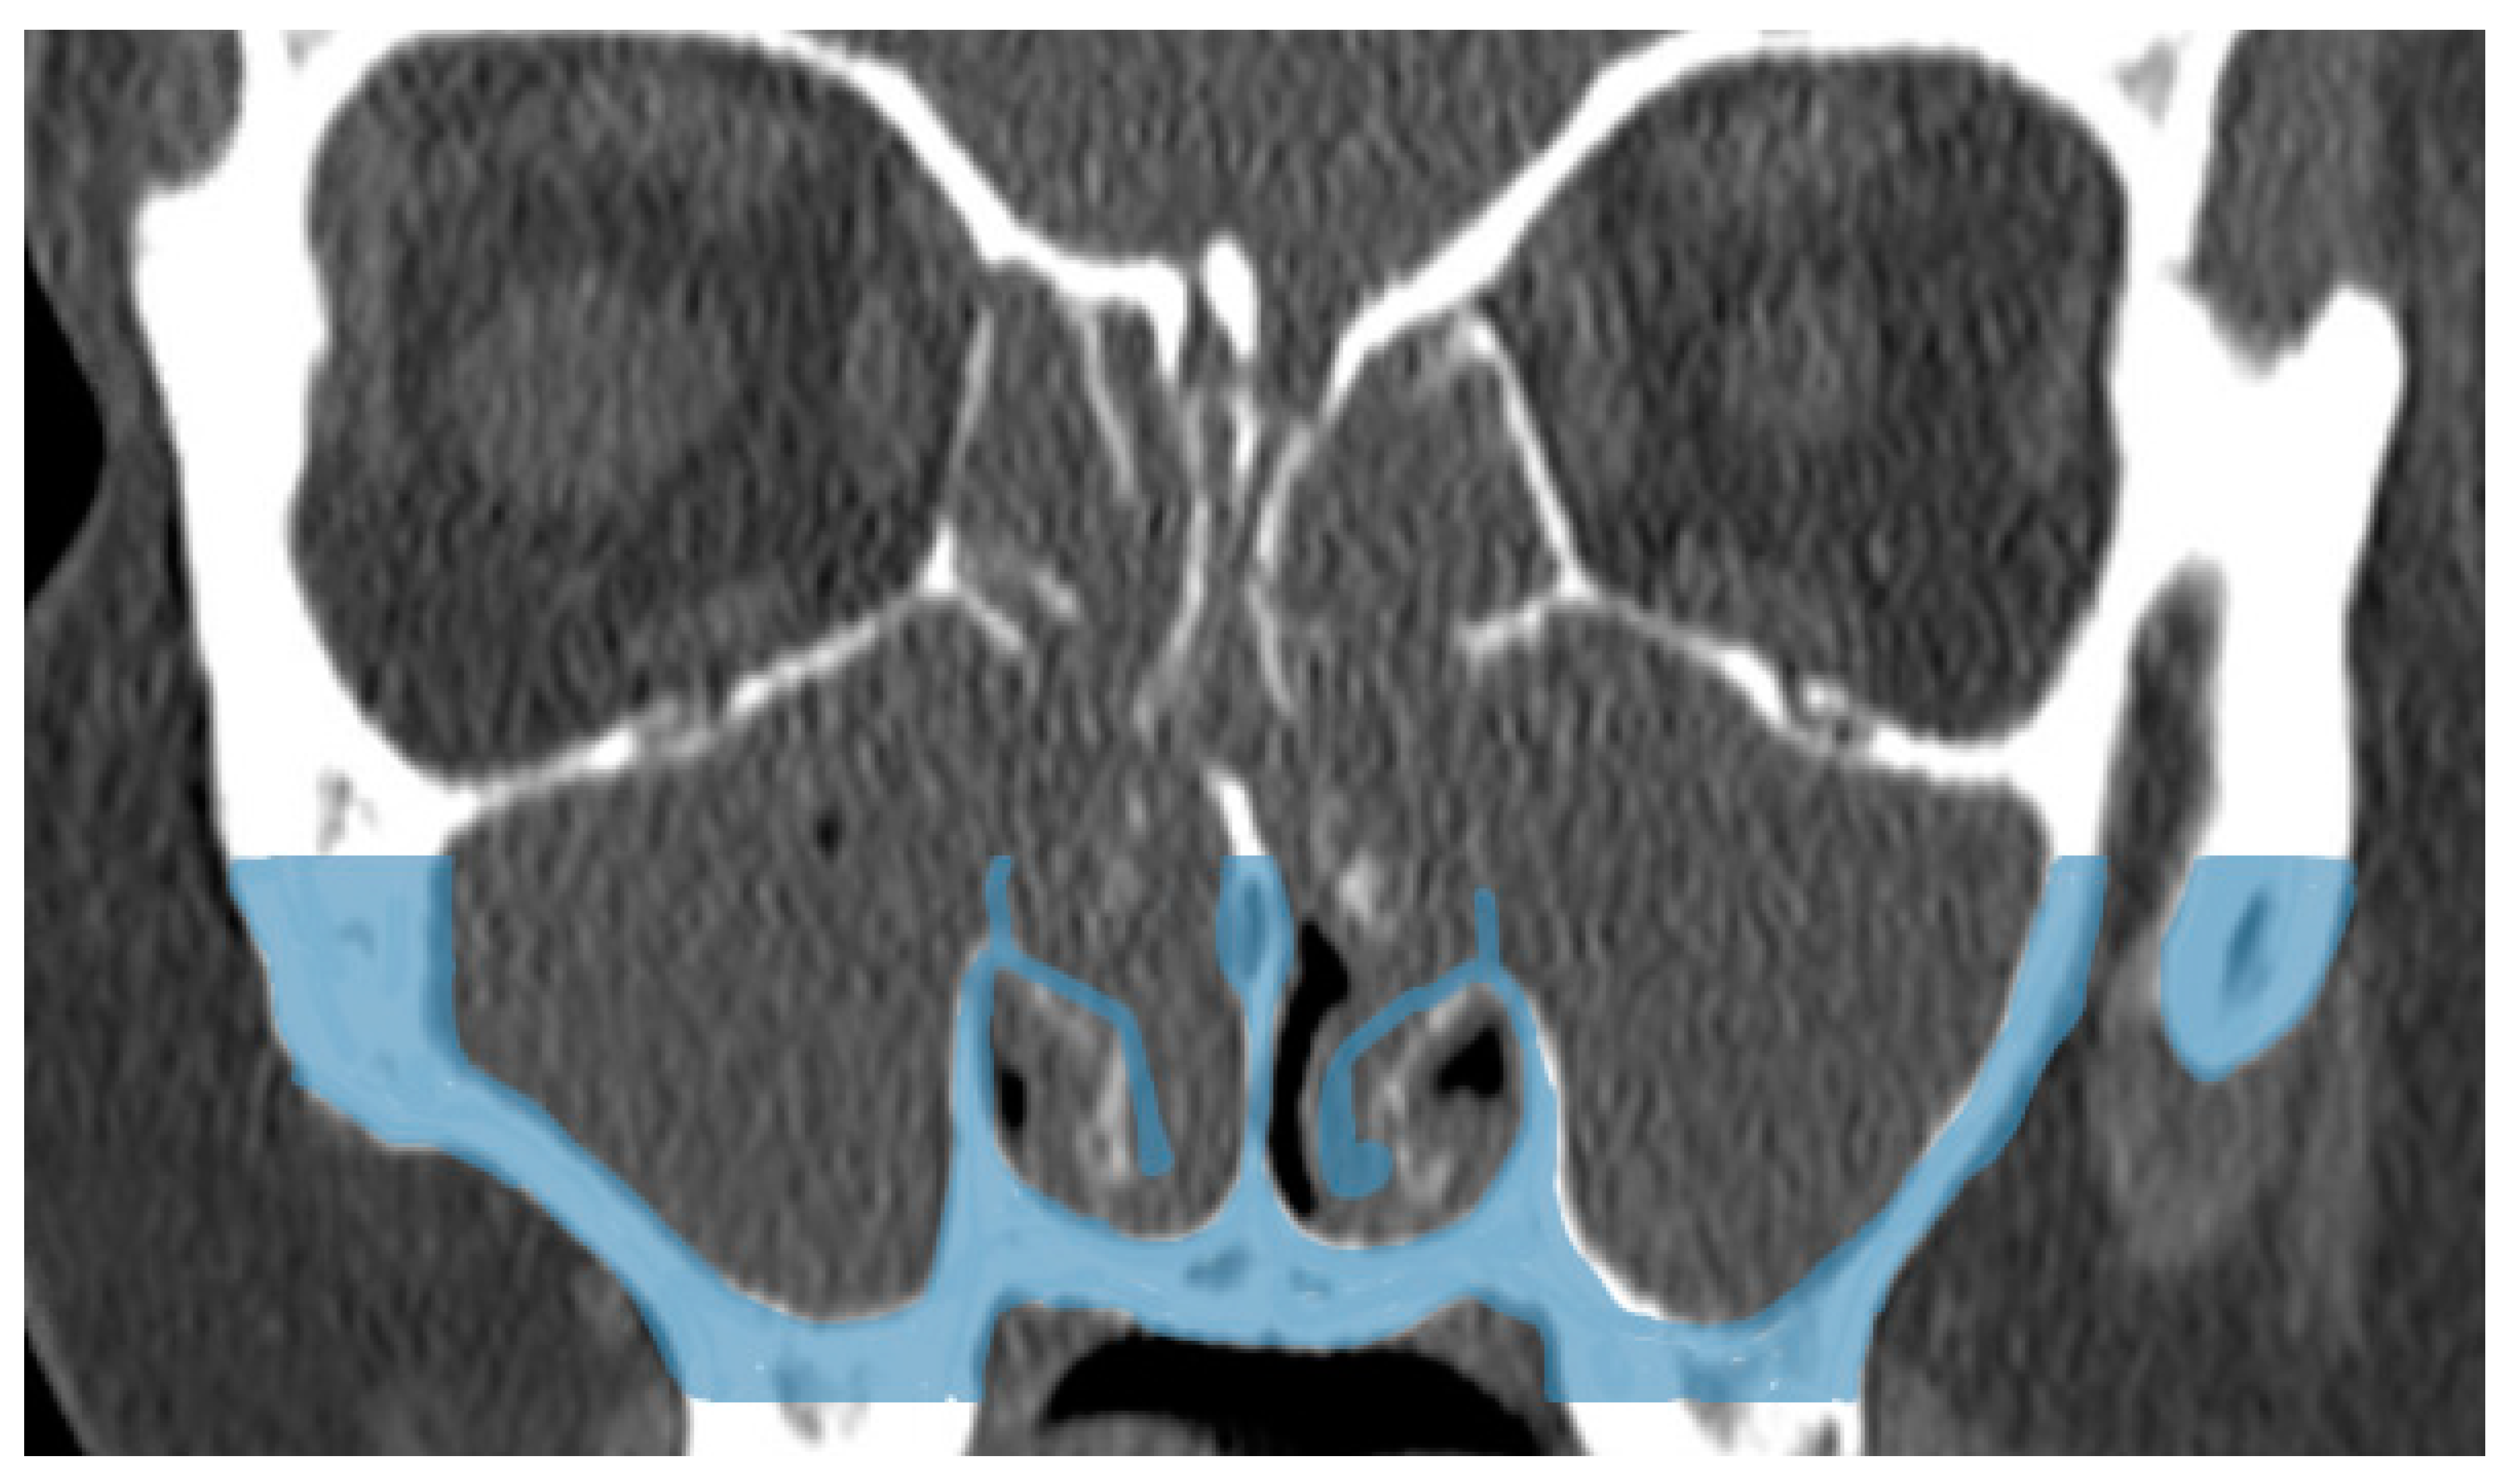

The results of our study show that IT outfracturing is an effective method for the lateralization of the IT and enlarging the nasal airway. Importantly, it appears this effect is sustained for years (Figure 3).

Figure 3. Showing merged computed tomography of pre-operative and post-operative images. Blue color shows the original position of the inferior turbinate prior to outfracturing.